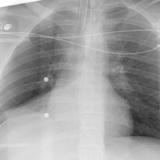

RLL Collapse 3 PA only

Date: 02/28/2004

Views: 3180